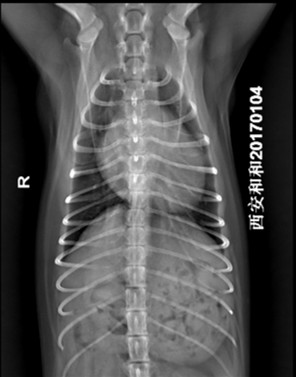

犬胸腔腹背位片示例 |

资源描述:动物仰卧,将前肢前拉、肘头外展,后肢自然摆放,脊柱拉直,胸椎与胸骨上下在同一垂直平面。投照范围从肩前到第一腰椎,投照中心在第5~6肋间隙(肩胛骨后缘)。

文件来源:西安京和动物医院有限公司